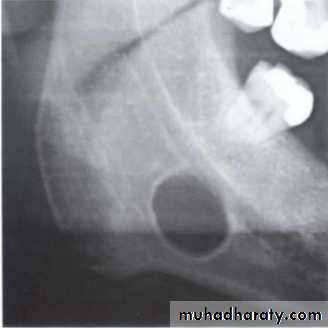

Corticated margins: thin radiopaque line of reactive bone at the periphery of a lesion eg. cysts

Lateral periapical cyst-well defined corticated margin